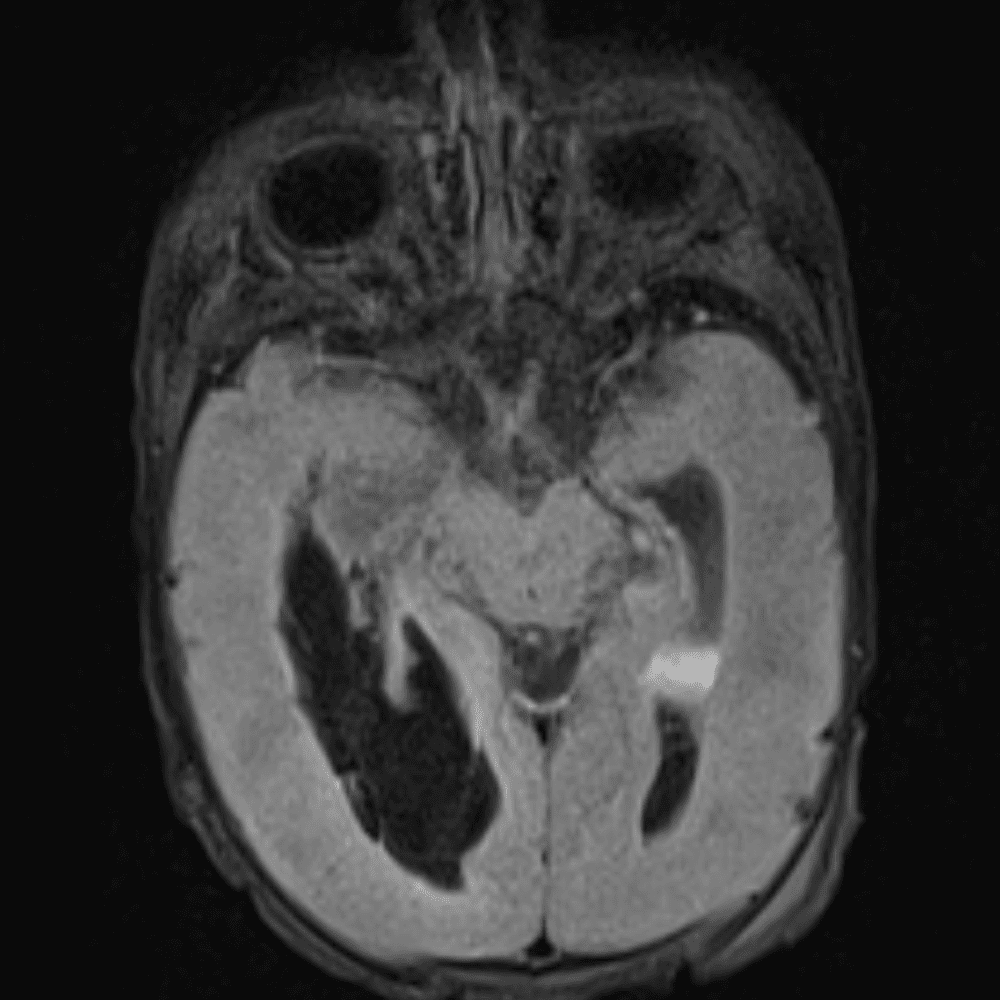

๋‹น์ง ์‹œ ํ”ํžˆ ๋ณผ ์ˆ˜ ์žˆ๋Š” ์‚ฌ๋ก€์˜ ์ „ํ˜•์ ์ธ ์˜ˆ๋ฅผ ํฌํ•จํ•ฉ๋‹ˆ๋‹ค.

39 ์‚ฌ๋ก€